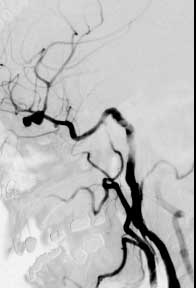

Findings: RCC angio shows the ICA follows an aberrent course, dipping inferiorly then laterally with no right A1 segment. A lobulated aneurysm involves the right MCA bifurcation. A second smaller aneurysm is present at the origin of the anterior temporal branch off the distal M1 segment. The normal left CC angiogram is shown for comparison.